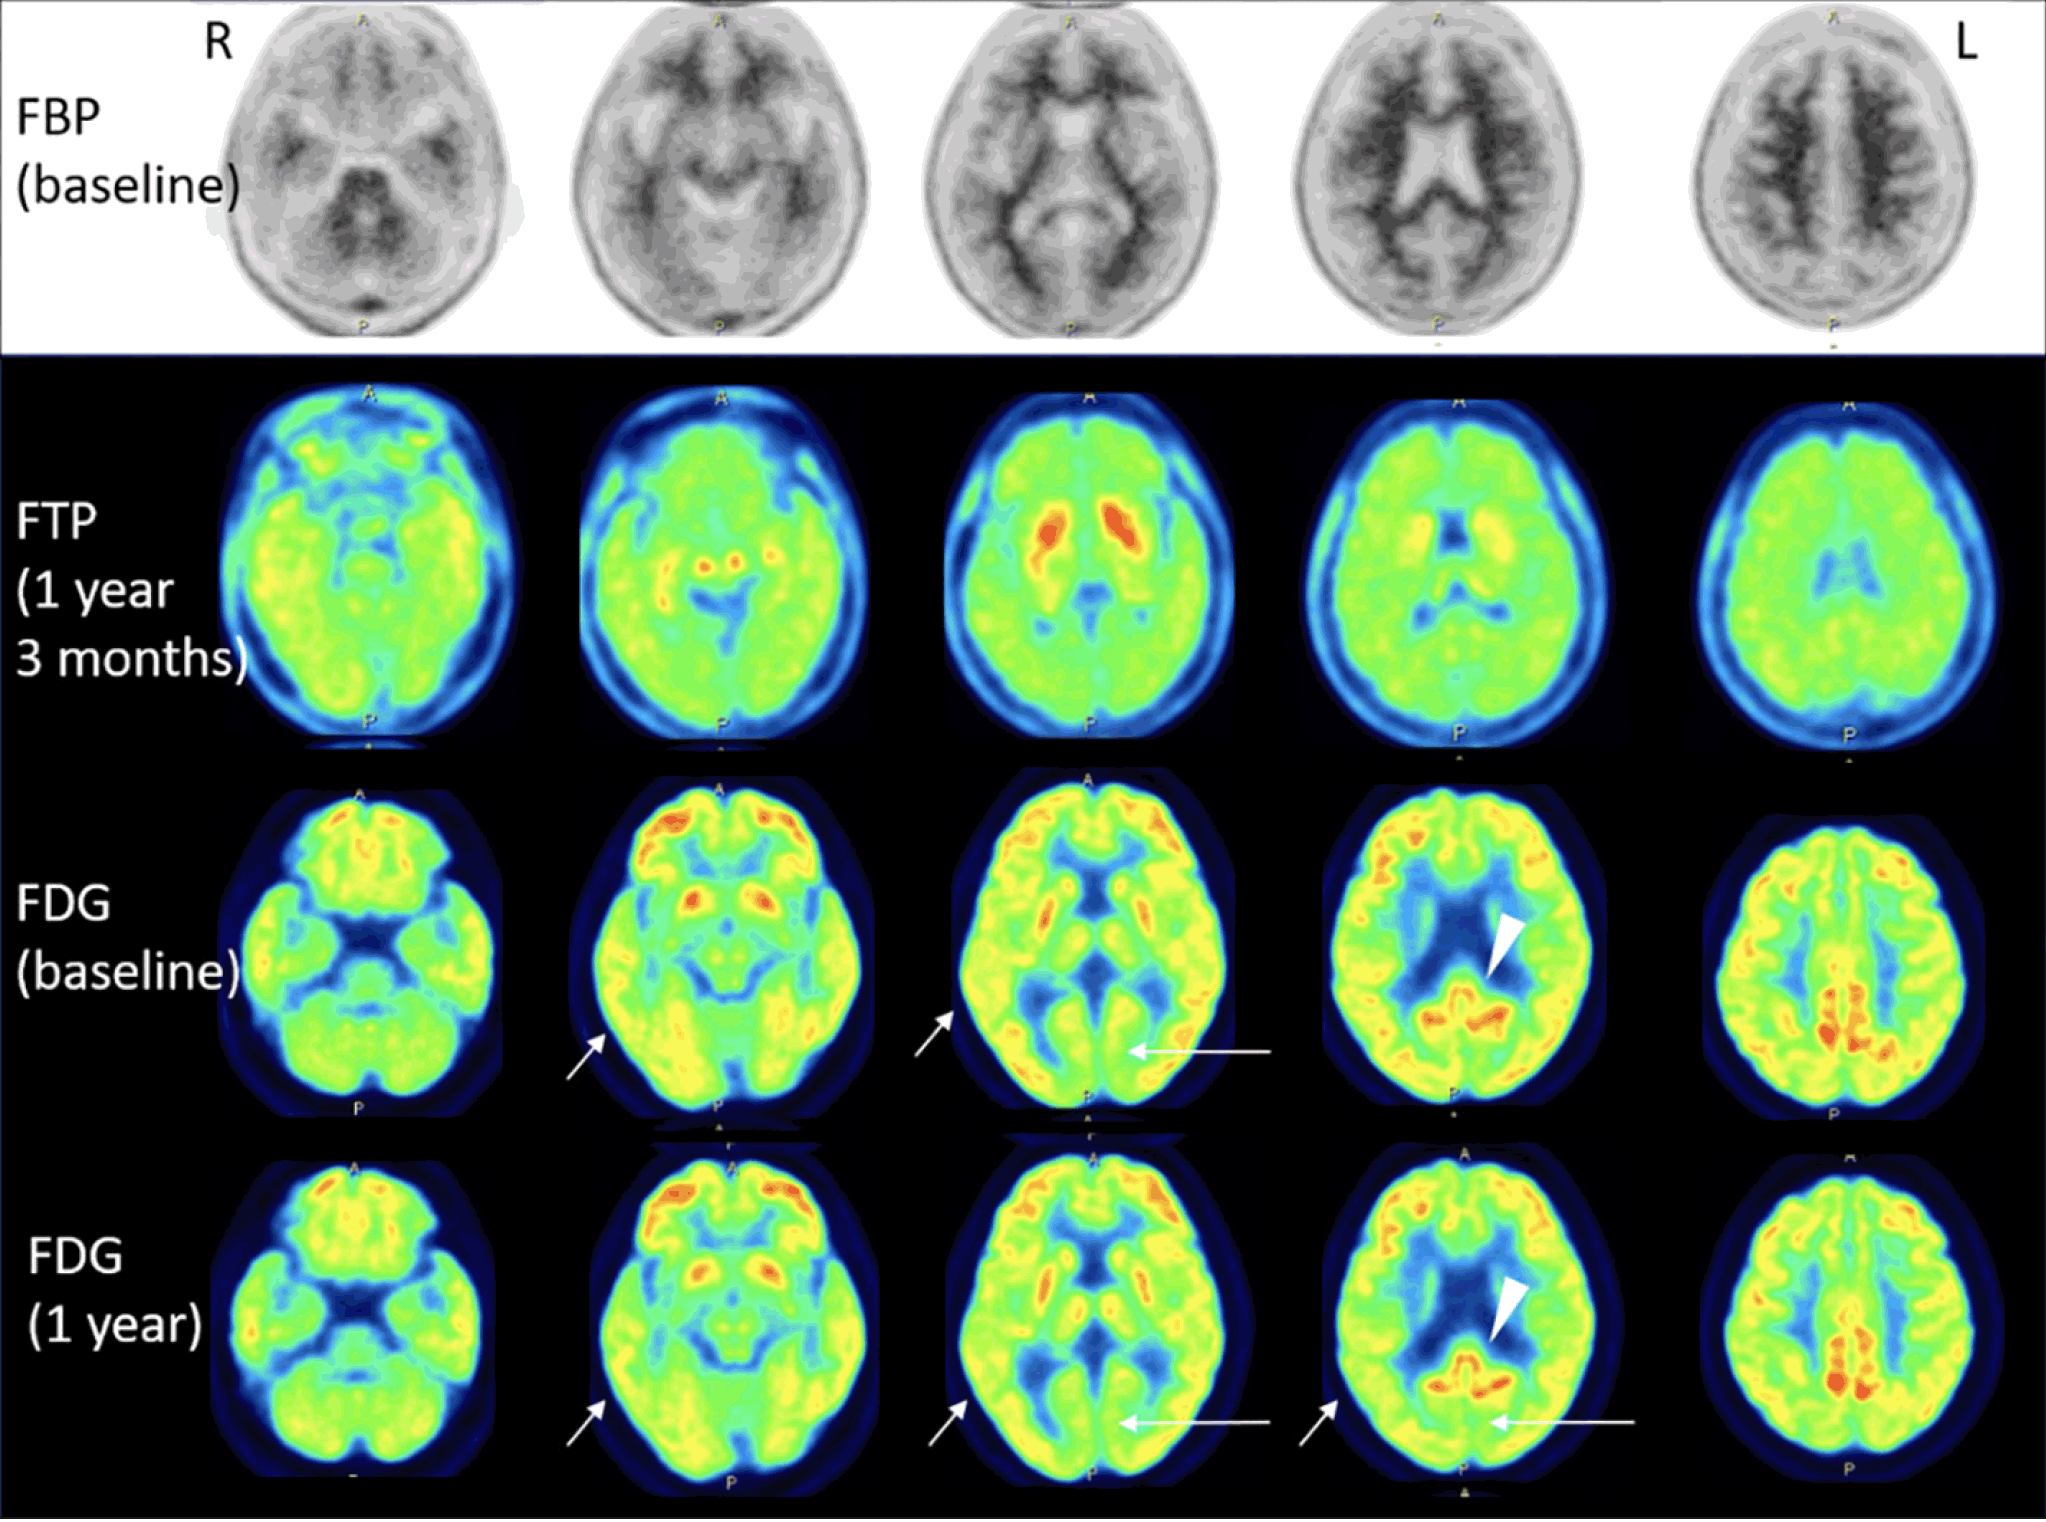

amyloid the journal of prevention of alzheimer s disease